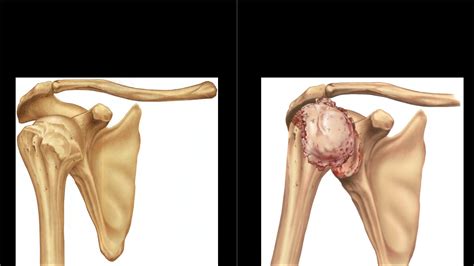

At its core, arthropathy refers to any injury or pathological state that involves the joints. A joint is the point where two or more bones meet, allowing for movement. When these structures are damaged by disease, wear and tear, or injury, the resulting condition is classified as an arthropathy. Because the term is broad, it can range from mild, temporary discomfort to severe, chronic, and debilitating diseases that significantly impair daily function.

• Osteoarthritis: A non-inflammatory, degenerative joint disease caused by the wear and tear of cartilage.

Deformity Changes in the alignment of the joint, common in advanced cases.